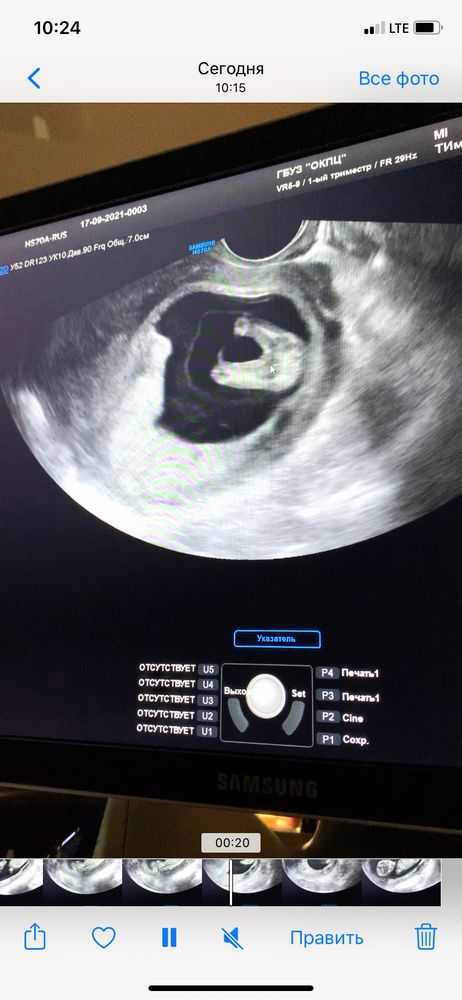

Первый скрининг)

БеременностьСходила на скрининг, все в норме я так счастлива ) вот теперь вопрос как думаете какой пол по бугорку ?)

Сходила на скрининг, все в норме я так счастлива ) вот теперь вопрос как думаете какой пол по бугорку ?)